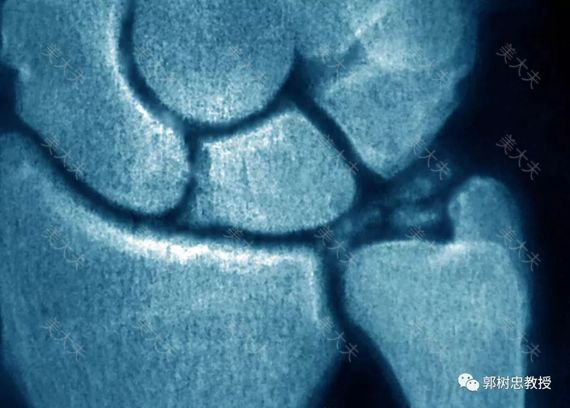

我过去造耳朵多数是三期手术,多数患者二期术后半年左右就做三期,少数病人等待数年后再造三期,有一个患者是十年后才来找我做三期的,我对这些患者的耳朵进行修整时,通常都要对软骨支架进行修整,手术中发现软骨的结构并没有发生变化,也从来没有发现软骨有钙化问题。

在临床上我们倒是遇到过极少数肋软骨本身已经钙化的病例,这个时候支架雕刻会困难一些,但远期效果并没有出现什么问题,多数还是能够维持早期的形状。